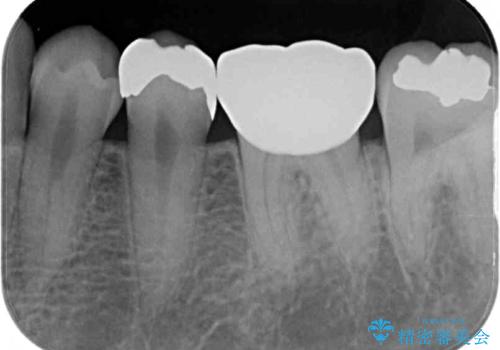

- 保険診療で装着した奥歯の白いクラウンの具合がよくないとのことで来院された患者様です。

保険診療で安価に白いクラウンが入れられるということで選択されたそうですが、装着後に痛みを感じたり、ものが挟まって不快であったりと不便が多いため、セラミッククラウンにて補綴治療を行うこととしました。

保険診療では、安価に白いクラウンを装着できる代償として、歯とクラウンの境目が不適合であったり、歯と歯の間にものが挟まりやすかったりと、不快な思いをされることがしばしばあります。

自費診療は、費用が高くなりますが、よい材料を選択したり、診療時間を十分にとったりできるため、単純に白いだけではない、良質なクラウンを装着することが可能です。